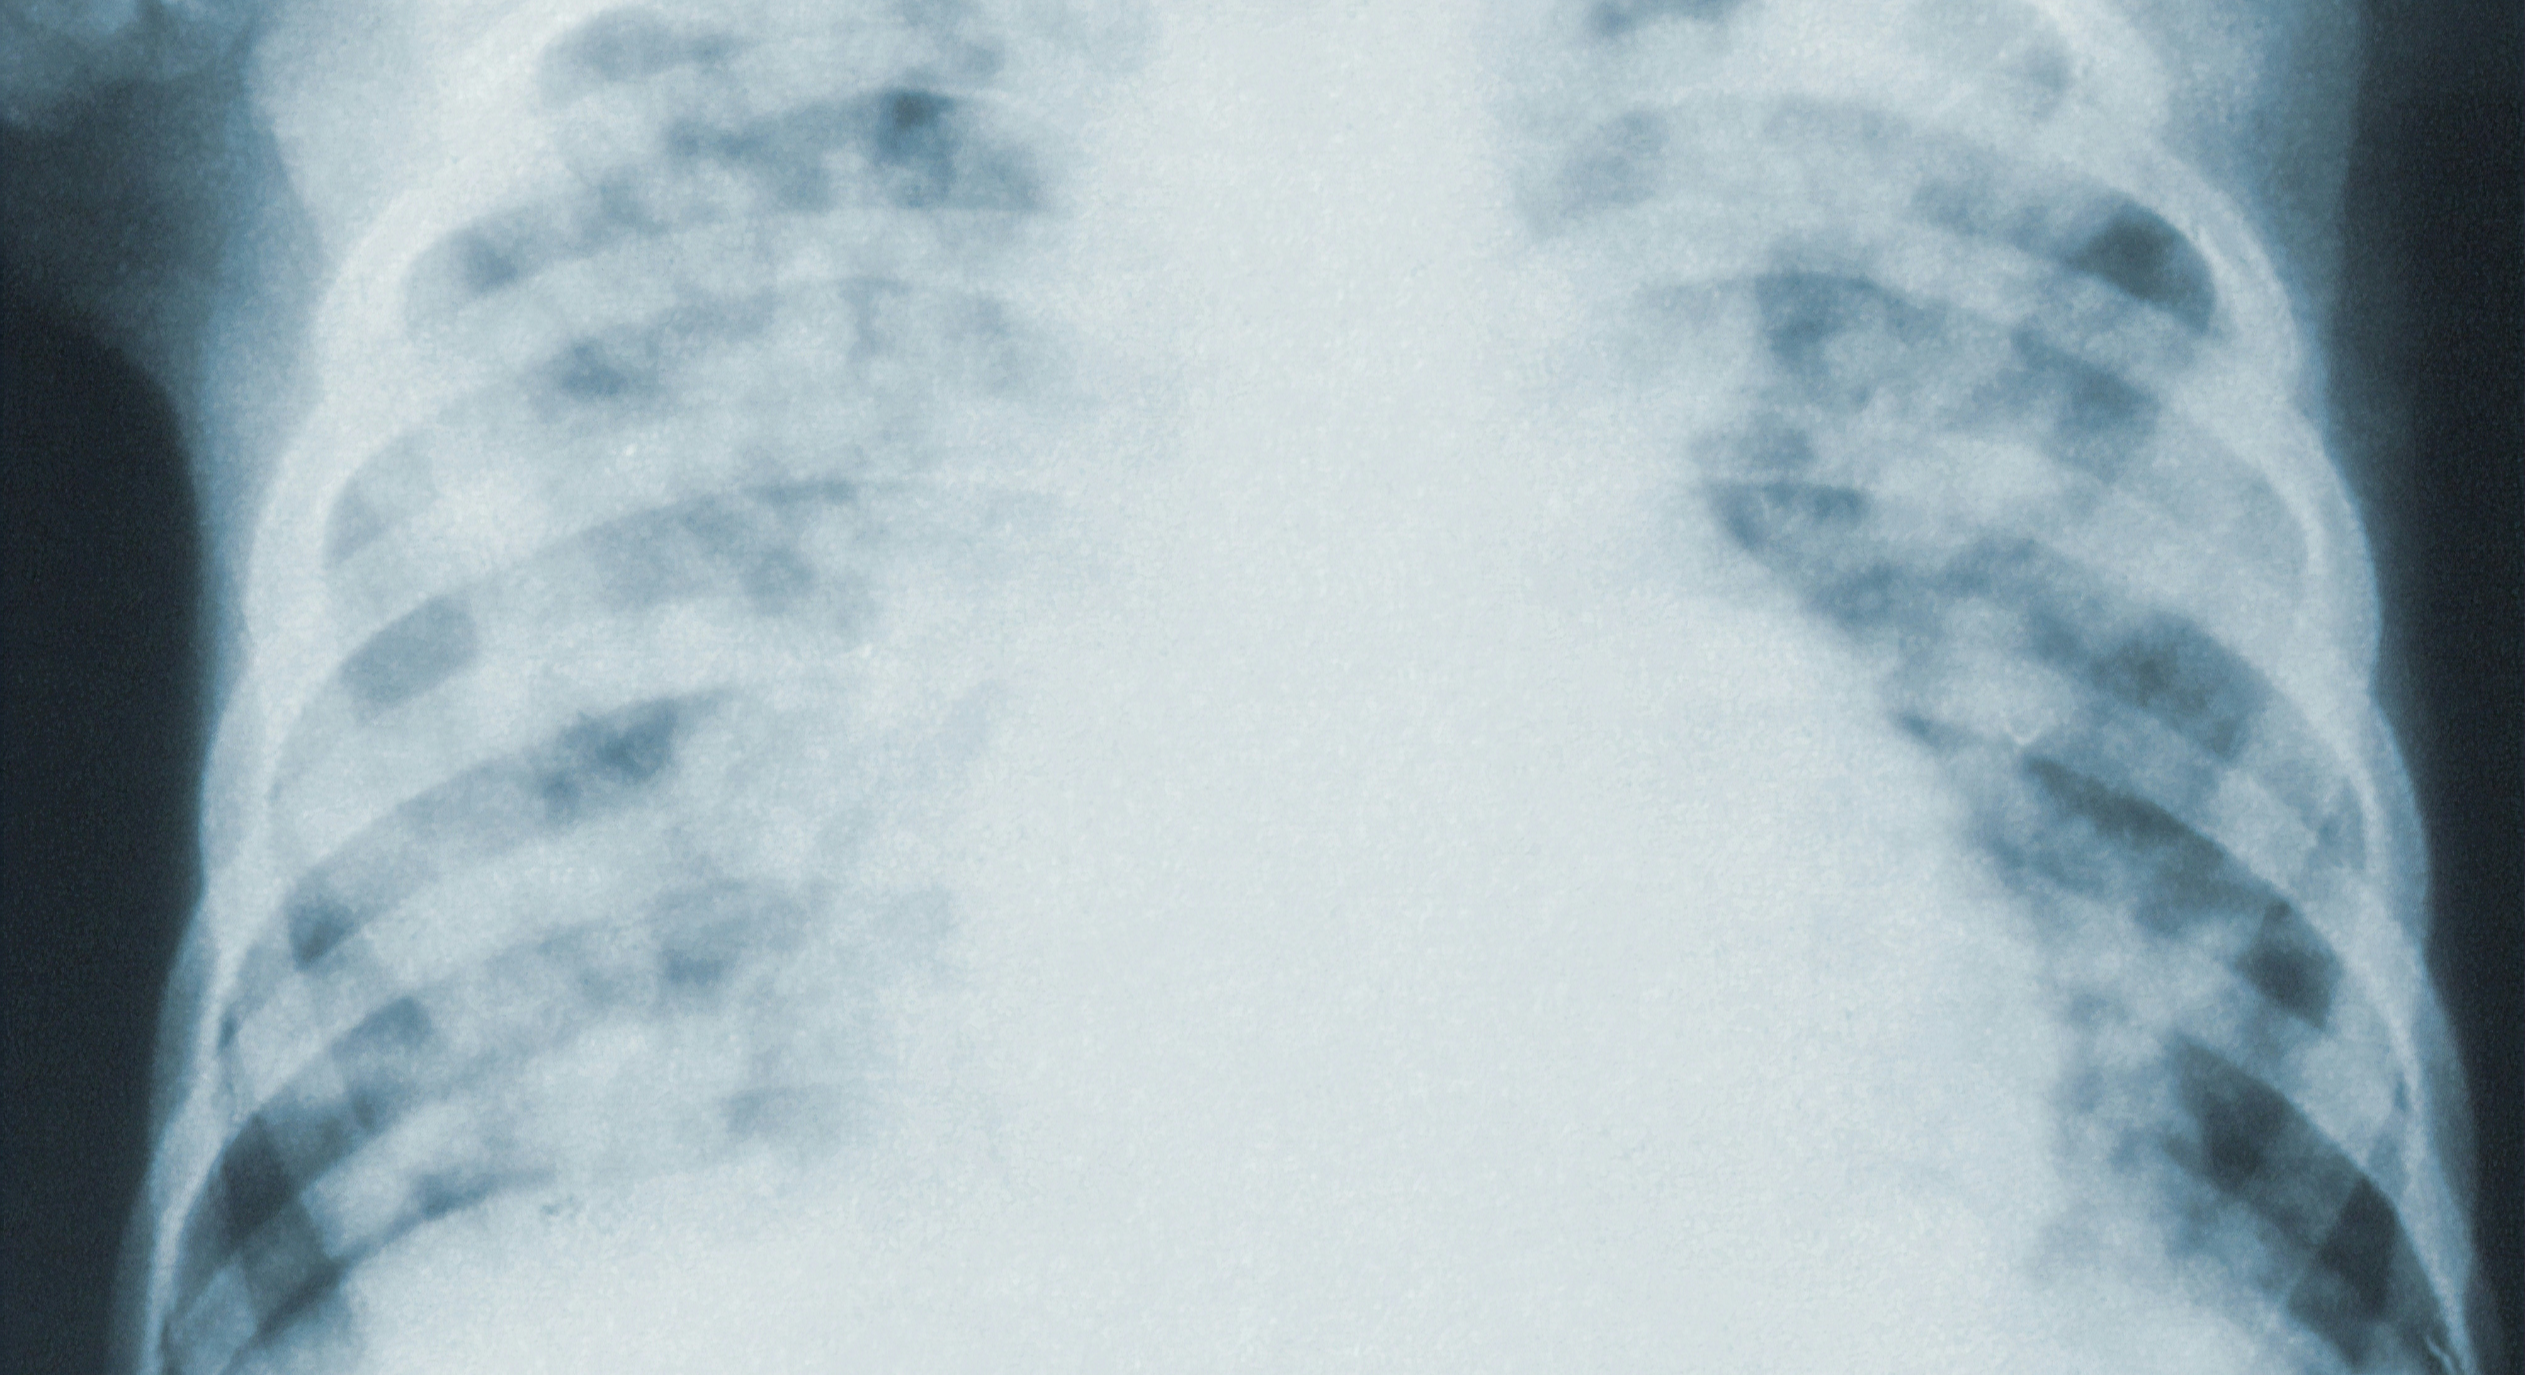

폐섬유증의 진단은 폐 기능검사, 흉부 X선, CT 스캔, 폐 기능평가 등의 다양한 검사를 통해 이루어집니다. 치료는 기저 원인을 다루는 것과 함께 스테로이드나 면역억제제와 같은 약물 치료, 호흡 재활, 산소 요법 등 다양한 방법의 치료가 진행될 수 있습니다. 일부 환자들은 폐 이식이 필요할 수도 있습니다.